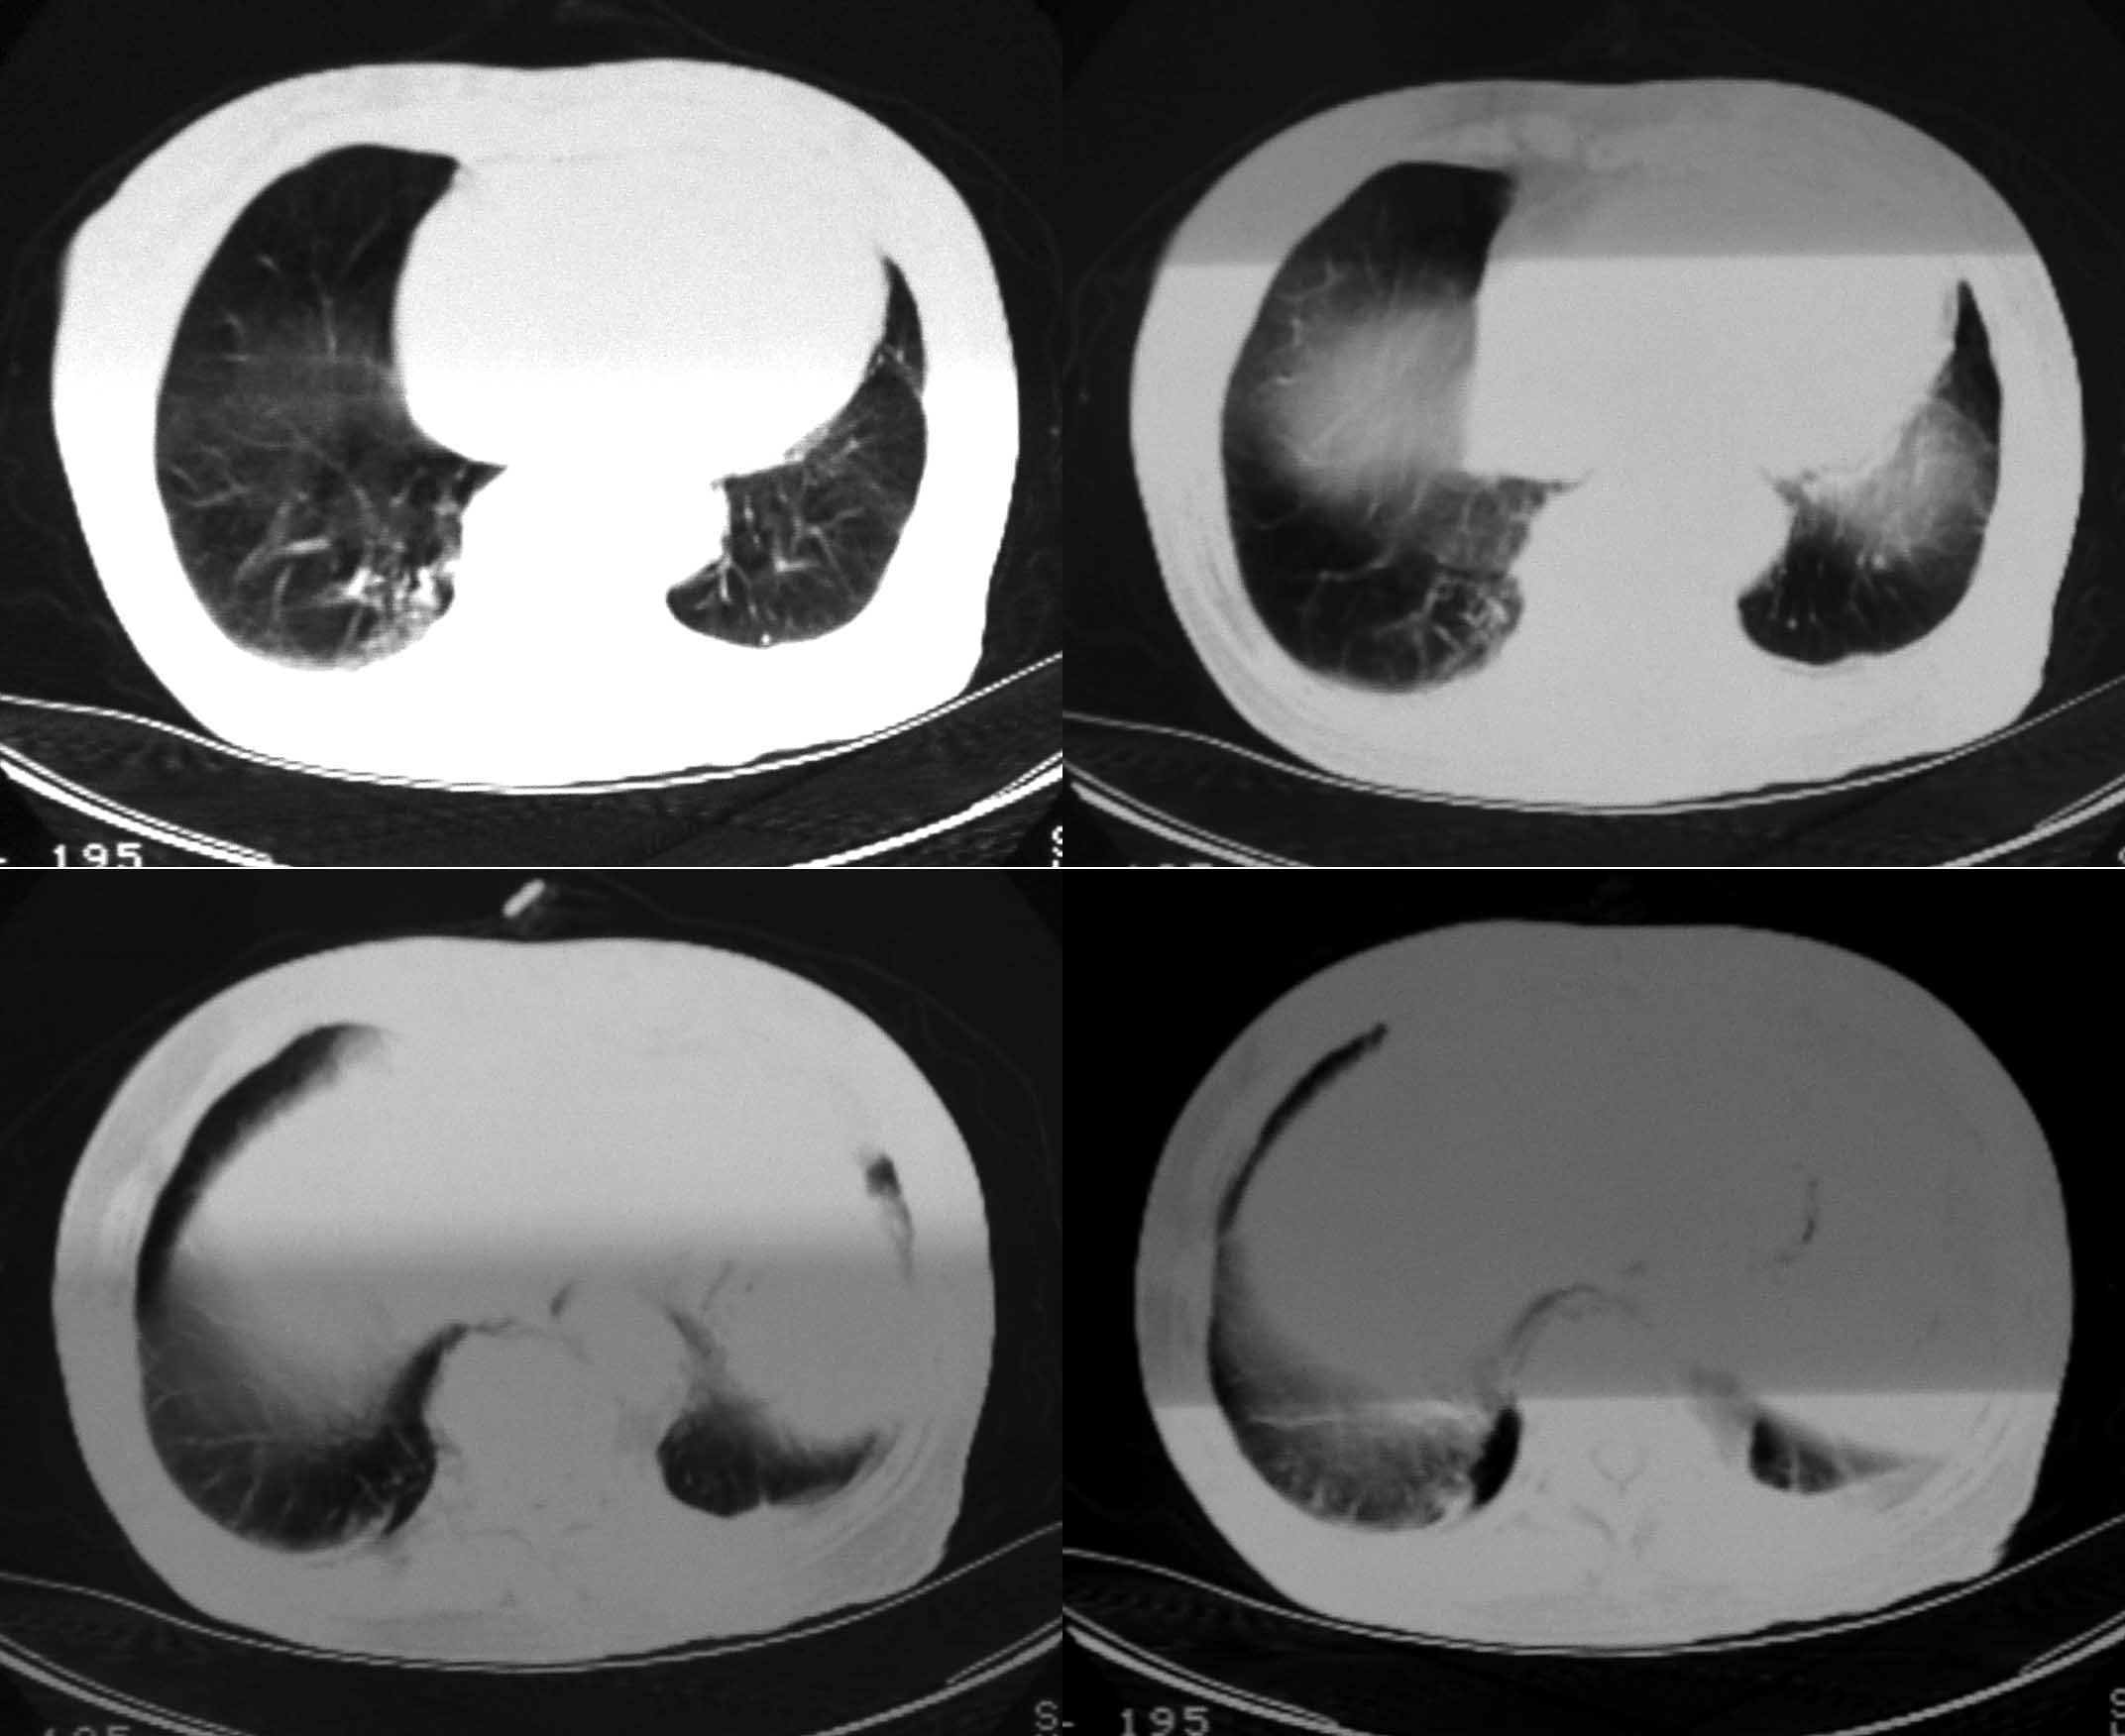

女69岁。时有咳漱、咳白色痰请老师们看看箭头所指是什么?ct值约-36.报告应该怎样写?谢谢!

考虑左后下胸内侧壁与胸膜之间脂肪影。

左后下胸内侧壁与胸膜之间脂肪影。

胸膜下脂肪影。